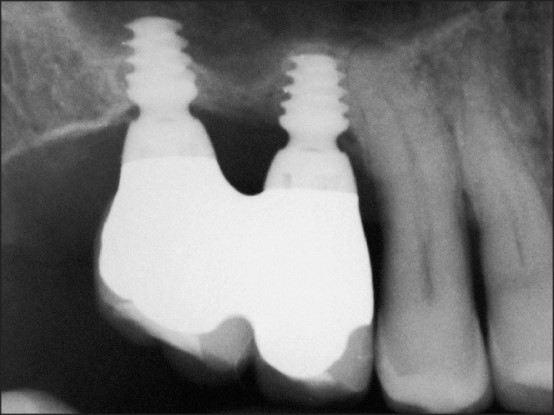

۲. انتخاب نوع و سایز ایمپلنت

بر اساس نتایج تصویربرداری، دندانپزشک طول و قطر مناسب ایمپلنت کوتاه را انتخاب میکند. طراحی و برند ایمپلنت هم در موفقیت نهایی نقش مهمی دارد.

۳. جراحی و قرار دادن ایمپلنت

در این مرحله، ایمپلنت کوتاه بهصورت دقیق در استخوان فک قرار داده میشود. به دلیل کوتاه بودن طول ایمپلنت، زاویه و جایگذاری باید بسیار دقیق باشد تا پایداری اولیه ایجاد شود. این کار معمولاً با بیحسی موضعی و بدون نیاز به جراحیهای سنگین انجام میشود.

جراح ماهر میتواند با استفاده از تصویربرداری سه بعدی (CBCT) تراکم و کیفیت استخوان را بهدرستی ارزیابی کند و تصمیم بگیرد که بیمار کاندید مناسب است یا خیر. - انتخاب نوع و زاویه ایمپلنت

تجربه و آشنایی با انواع ایمپلنتها به پزشک کمک میکند بهترین طول، قطر و زاویه را انتخاب کند تا حداکثر پایداری حاصل شود. - کاهش ریسک عوارض